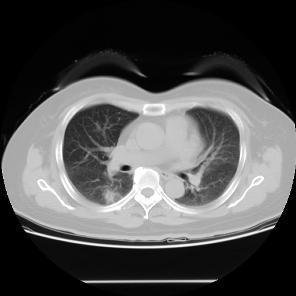

患者,女,57岁,因“右肺占位”于2015-09-17 15:08入院。 患者缘2月前体检无意发现右肺占位,伴随症状:无咳嗽、咳痰、无胸闷、胸痛、气短,无头晕、视物旋转,无恶心、呕吐,无腹痛、腹泻,无尿急、尿频、尿痛,2015-7-1 CT示:1.右肺上叶前段及下叶背段结节伴实变,右肺下叶结节见支气管气相征,考虑炎性病变可能,建议治疗后复查除外肿瘤性病变;双肺多发炎症;2.双侧胸膜肥厚;肺动脉增宽,提示肺动脉高压;3.肝左外叶小囊肿;4.甲状腺双叶增大,考虑为甲状腺肿,请结合临床。2015-9-2复查CT示:1.右肺上叶前段结节较前片无明显变化;右肺下叶背段结节较前片增大,建议进一步检查除外肿瘤性病变;双肺多发炎症较前片吸收;2.双侧胸膜肥厚;肺动脉增宽;3.肝左外叶小囊肿;4.甲状腺肿大,同前片。以“右肺占位”收住院,自发病以来,食欲减低,体重无明显下降,大小便无异常。

患者无任何症状,体检发现肺部小结节影,观察2月,未见缩小,似有轻度增大,入院后经CT引导下肺穿刺活检提示高分化腺癌,行手术治疗。 周围型肺癌早期影像学表现为孤立的肺内结节或肿块,通常有分叶征,毛刺征,空泡征,支气管充气征,坏死液化或空洞形成。此患者仅表现为淡薄的渗出影,小结节影,观察2月没有变化后,经穿刺证实肺癌,因此对肺部小结节影,斑片影,不吸收,无钙化的要特别注意肿瘤可能。